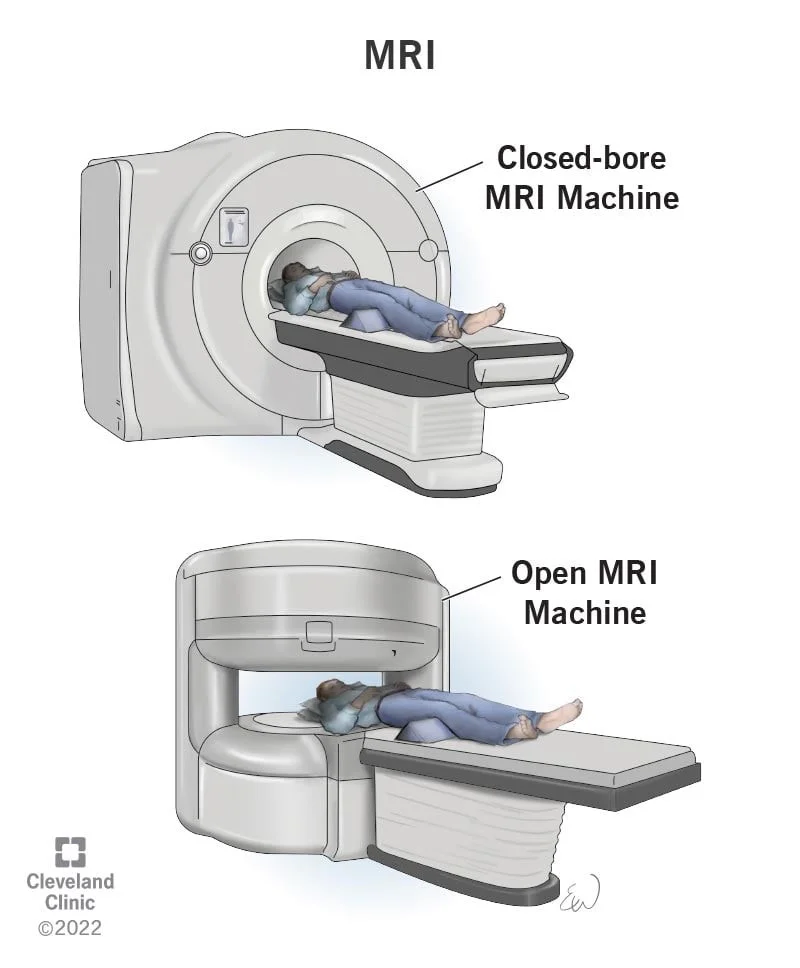

تصویر برداری رزونانس مغناطیسی (MRI یا Magnetic resonance imaging)

مانند سی تی اسکن، MRI تصاویر دقیقی از بافتهای نرم بدن نشان میدهد اما MRI از امواج رادیویی و آهنرباهای قوی به جای اشعه ایکس استفاده میکند. این آزمایش به ندرت در HL استفاده میشود اما اگر پزشک نگران گسترش به نخاع یا مغز باشد، MRI برای بررسی این نواحی بسیار مفید است.